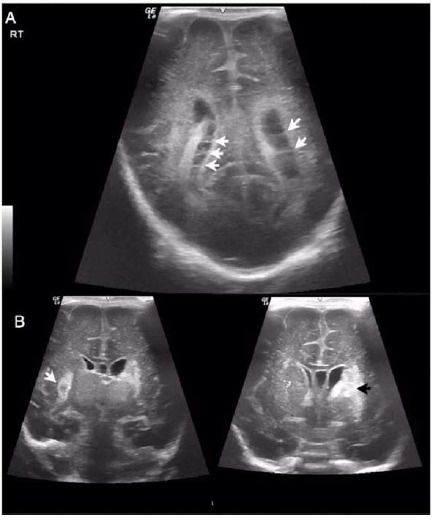

Case presentation: A set of preterm male triplets born at 30 weeks of gestation were admitted to the neonatal intensive care unit. At two weeks of age, the infants showed clinical manifestations of LOGBS sepsis, including septicemia. Additionally, one of the triplets developed meningitis complicated by hydrocephalus, while another developed necrotizing enterocolitis (NEC). Concurrently, their mother was diagnosed with mastitis and her breast milk cultures tested positive for GBS. The triplets were treated with systemic antibiotics. However, triplet B subsequently required a ventriculoperitoneal shunt for hydrocephalus management, and triplet C underwent laparotomy for NEC treatment.